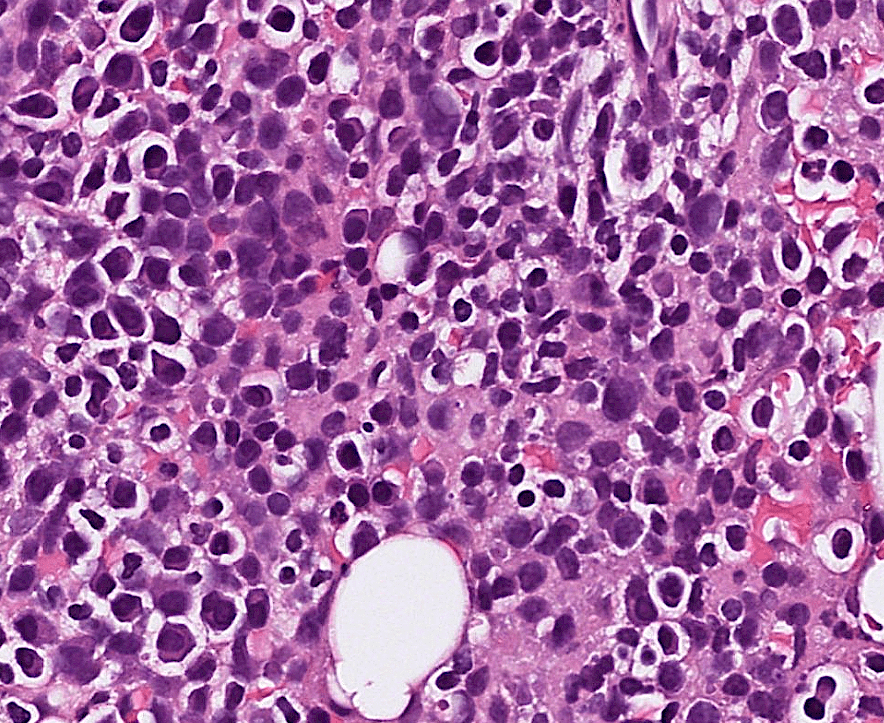

Organ: Lymph node

Diagnosis: Lymphoid hyperplasia

Descriptions:

- Increased number and size of follicles

- Follicles have distinct mantle zones and polarized germinal center

- Normal cell composition and tingible-body macrophages in the follicles